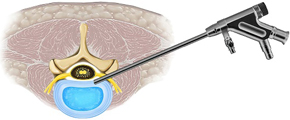

MED法は低侵襲手術として広まっている方法です。手術による傷口は2cm程度と小さい為、身体にかかる負担が小さく、治療に要する入院期間(およそ7日間程度)も短い為、早期社会復帰が可能な手術です。手術方法には腰椎椎間板ヘルニアに対するMED法(内視鏡下腰椎椎間板摘出術)、腰部脊柱管狭窄症や腰椎変性すべり症に対するMEL法(内視鏡下腰椎椎弓切除術)があります。

FESS法は、MED法で用いた直径16mmのtubular retractorを直径さらに低侵襲にした手術です。直径7~10mmのtubular retractorを用いて手術を行います。水を還流し良好な視野を保ちながら手術を行います。FESS法のために開発された小さな鉗子・ラジオ波バイポーラ・ドリルを用いて経皮的にヘルニアを摘出し、神経を圧迫する靭帯や骨を切除する方法です。現在、椎間板ヘルニアや腰部脊柱管狭窄症、頚椎症性神経根症などの頚椎病変の一部まで適応があります。

上図のように、FESS法には2つの経路があります。側方経路が椎間孔アプローチ、後方経路が経椎弓アプローチといわれています。手術術式はそれぞれのケースで異なっています。

上図は椎間孔アプローチです(左図)。内視鏡を椎間板に平行にして椎間板ヘルニアに近づけます(中央図)。椎間板ヘルニアを摘出しています(右図)。